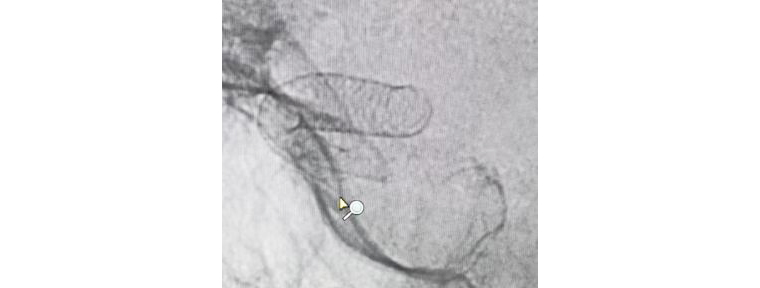

團隊人員術(shù)前充分準備,術(shù)中配合默契,支架順利釋放,造影觀察支架貼壁良好,瘤腔內(nèi)造影劑滯留,載瘤動脈通暢,手術(shù)非常成功。術(shù)后兩天,患者平穩(wěn)出院,對治療效果很滿意。

支架成功釋放